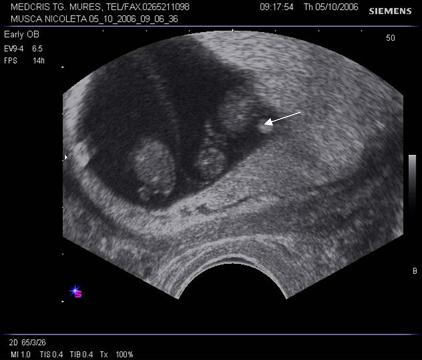

Fig nr 6 Decolare de pol inferior ( cu sageata ) la o sarcina de 7 sapt

Fig. nr. 66. Aceeasi sarcina, ca in figura precedenta, la 12 saptamani , fara imagini patologice la polul inferior ovular, marcat cu sageata